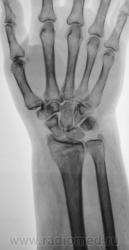

Травма.   Пациент направлен на рентгенографию лучезапястного сустава.

СЛУЧАЙ № 1.